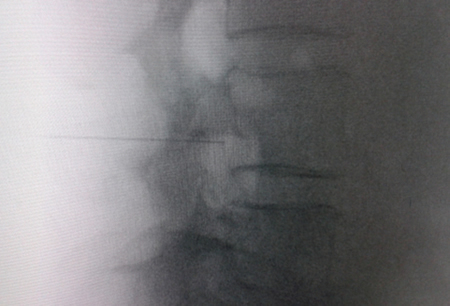

Access by transforaminal route is the most widely used (4). The patient is placed in prone position with an abdominal pillow to reverse physiological lordosis. The most commonly used RF needles or cannulas are 20 or 22 G diameter and 98 mm long with 0.5 or 1 cm active tip. Following asepsis with alcoholic chlorhexidine and placement of sterile fields, radiological approaches in anteroposterior, oblique and lateral incidence are performed. In anteroposterior incidence and moving the arc in cranio-caudal direction, the double arc of the lower vertebral edge is deleted. In oblique incidence between 20 and 30 degrees ipsilateral to the DRG to be treated, the classic image described as “Scotty Dog” will be displayed, which is the result of bringing the articular facets and the spinous process closer to the contralateral side. The entry point will then be immediately below the pedicle. After local anesthesia with 1 % lidocaine, the needle will be inserted following a tunnel vision and will not advance beyond half of the pedicle in this projection to prevent neural injury. In lateral projection, it will be inserted into the roof of the neuroforamen (Figures 1 and 2) but the final location will be determined by sensory-motor nerve stimulation. Sensory stimulation is to cause paresthesia or pain in the affected territory with stimulation between 0.3-0.6 v. During motor stimulation fasciculations can be caused in the affected territory with a voltage of twice that necessary to cause paresthesia. If an intraganglionar denervation, promulgated by some authors, is desired, both sensory and motor stimulation will be positive at less than 0.3 v. As this is a more painful procedure, it is advised to administer local anesthetics after the painful stimulus and before treatment. The impedance should be kept below 450 ohms, which is achieved by infusing saline before proceeding with RF (4). The use of contrast is good practice, as it rules out the intravascular and intrathecal position of the radiofrequency cannula.

Fig. 1. Lateral radiological view showing a radiofrequency cannula at the anterosuperior angle or roof of the neuroforamen, approximate topography of the dorsal root ganglion

Fig. 2. Anteroposterior radiological view of a radiofrequency cannula placed in neuroforamen L4-L5, in the so-called safety triangle, after contrast injection. A thickening of the radiculogram is observed at the roof of the neuroforamen, which may correspond to the dorsal root ganglion of L4